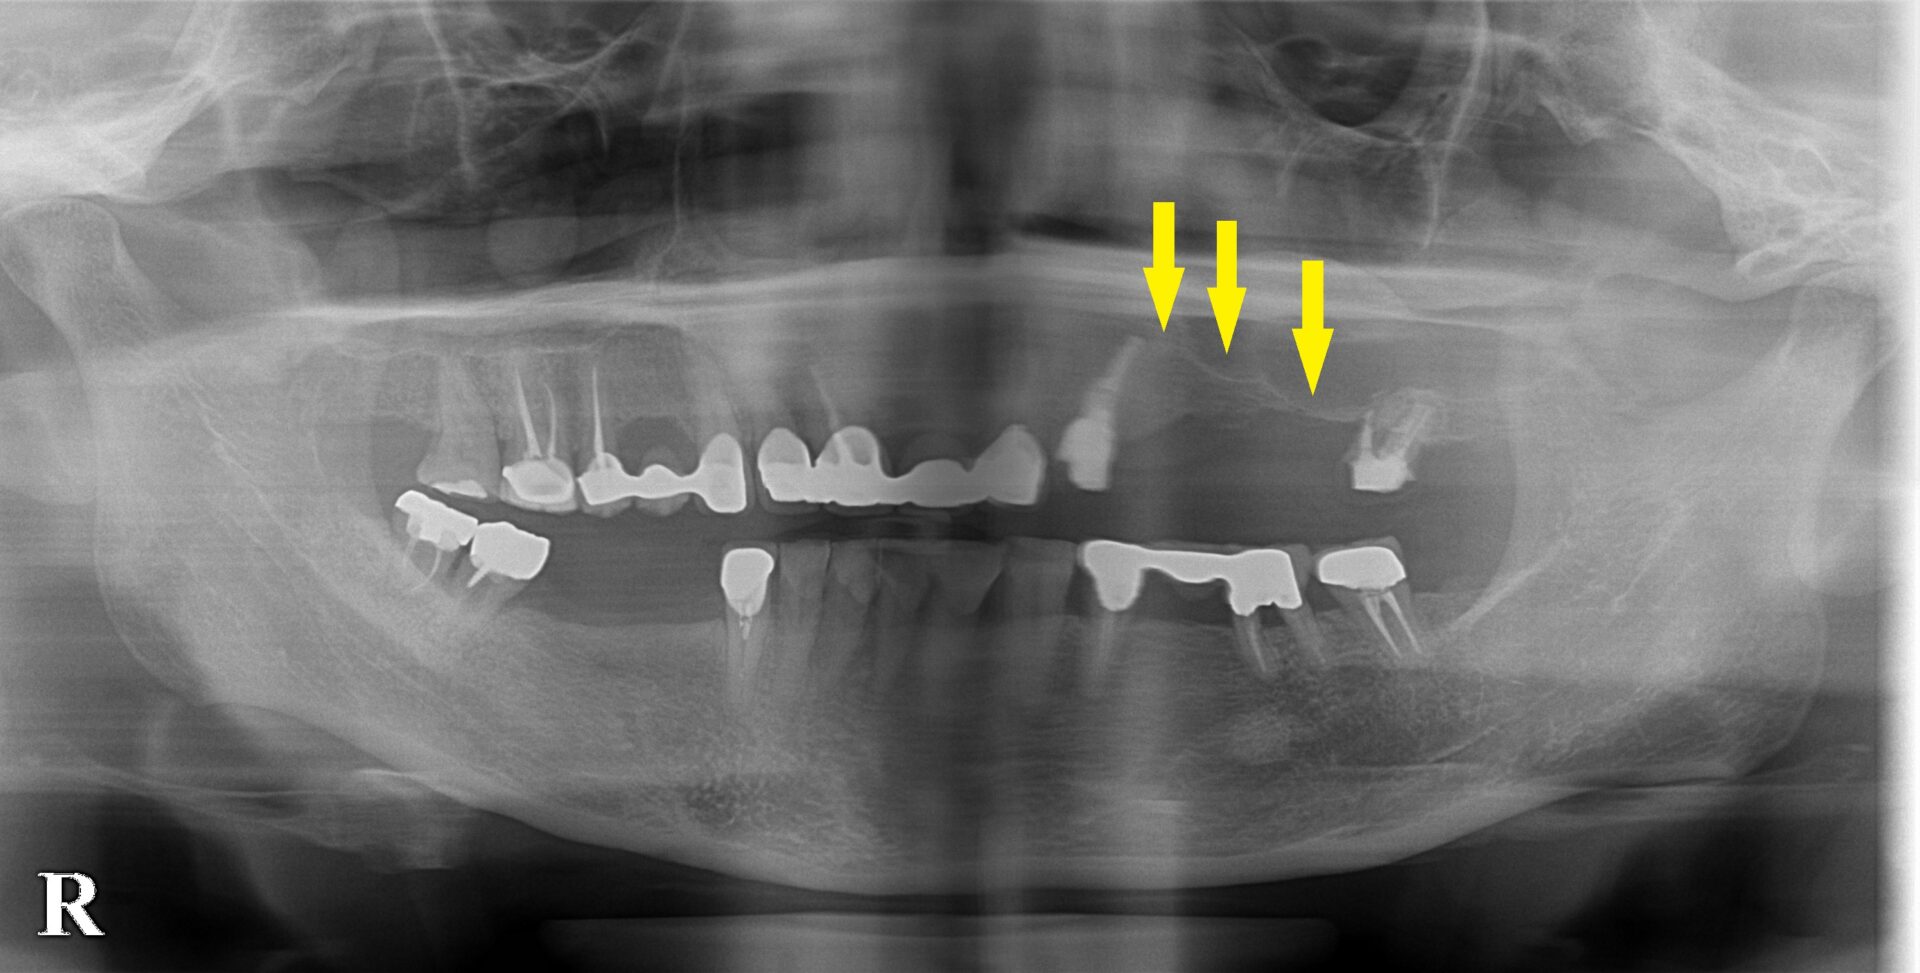

サイナスリフトと側方への骨造成、両方行った症例

まだお若いのですが、右下顎と左上顎の臼歯を多数抜歯され、義歯を作製されたのですが、とても受け入れがたいもので、使用していなかったそうです。

インプラント治療を希望されたのですが、左上顎は骨が非常に薄くて、できないと言われたそうです。

左臼歯に、3歯は必要と思われましたが、CTを見ると、1本目は骨の幅が狭く、2本目、3本目は骨の高さが足りません。